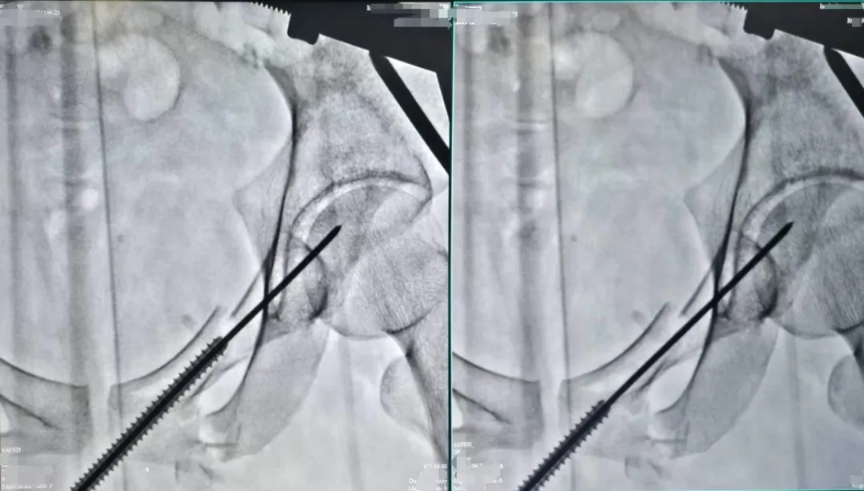

術中透視(上)

針對小陳這樣的案例,使用的經皮恥骨支螺釘內固定術是一種髓內固定技術,在治療骨盆前環損傷中得到了越來越廣泛的應用,常用于恥骨上支骨折和髖臼前柱骨折。經過實踐分析,這是治療單側恥骨骨折的最佳治療方式,具有手術創傷小、術中出血量少、固定強度大、并發癥少及功能恢復快等優點。